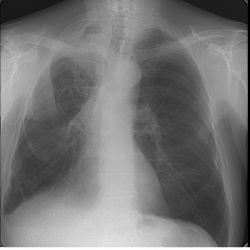

Жалобы на онемение правой руки со дня медработника, ,одышки ,кашля нет.

Жалобы на одышку. Архив 6 мес назад без данных изменений. Из анамнеза Са МЖ.Ваши мнения коллеги)

Анамнез Са в/доли правого легкого, в/лобэктомия. Выписан недавно, особо там не возились.Ваши мнения о чем можно думать по рг-картине.